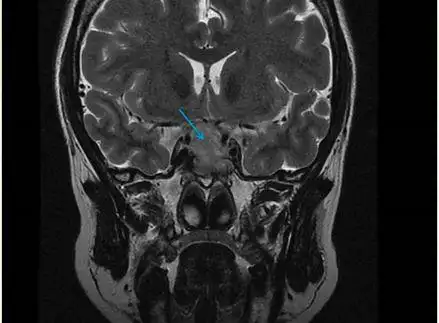

垂体 mri 平扫